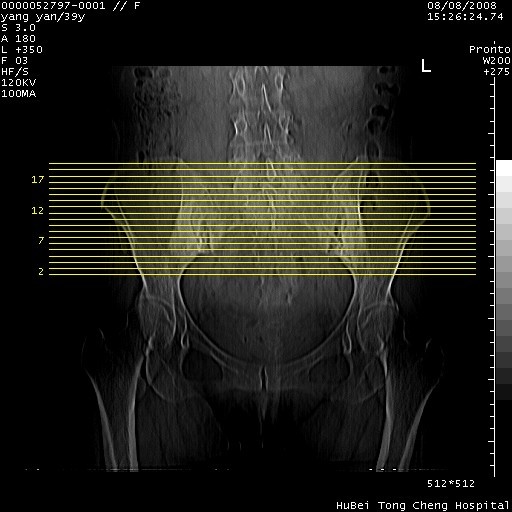

患者 女,39岁。因外伤检查,偶然发现。

典型!双侧骶髂关节致密性骨炎。

典型!病变主要累及双侧髂骨。常见于育龄期妇女。

致密性骨炎,一般不跨越关节面,可是这个骶骨关节面也有硬化。

髂骨致密性骨炎系一种以骨质硬化为特点的非特异性炎症,有高度致密的骨硬化现象,尤其以髂骨下2/3更为明显,但关节间隙则无改变。因位于骶髂关节,且该关节症状明显,故又称之为“骶髂关节致密性骨炎”。 本病90%以上为中年女性,以妊娠后期、尤其分娩后为多见,亦可见于尿路或女性附件慢性感染后,或盆腔内其他感染。此外,臀骶部的外伤亦可诱发或引起本病。  妊娠、分娩及外伤均可引起骶髂关节韧带的撕裂而易使局部的血供受阻。因此早期局部呈现充血、水肿及渗出增加等,渐而局部出现增生与变性反应,随着胶原纤维的致密化而向硬化演变;血管形成厚壁血管,易闭塞而引起髂骨耳状面处缺血和缺氧,骨质呈现硬化性改变,以致手术时局部出血较少。骶髂关节囊壁显示纤维增生、弹性降低及松动样改变。继发于盆腔内炎症者亦出现相类似的病理改变,可能系细菌内毒素作用所致。